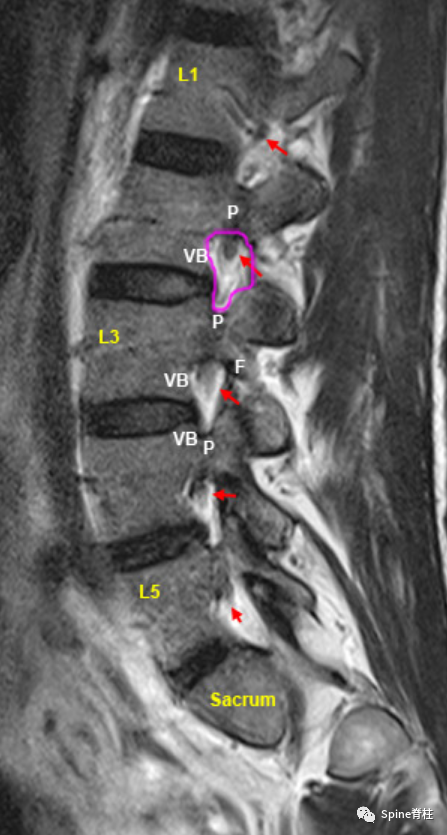

腰椎椎间孔矢状位(Foraminal-Sagittal Region)是一个位于旁矢状位外侧的区域,可很好的显示椎间孔的边界(粉红色圆圈):顶部和底部分别由上下椎弓根(P)组成。后边界由下位脊椎的上关节突组成,前边界由椎间盘和椎体(VB)组成。注意,椎间孔因高脂肪含量而呈高信号,而出口神经根(红色箭头)呈低信号。